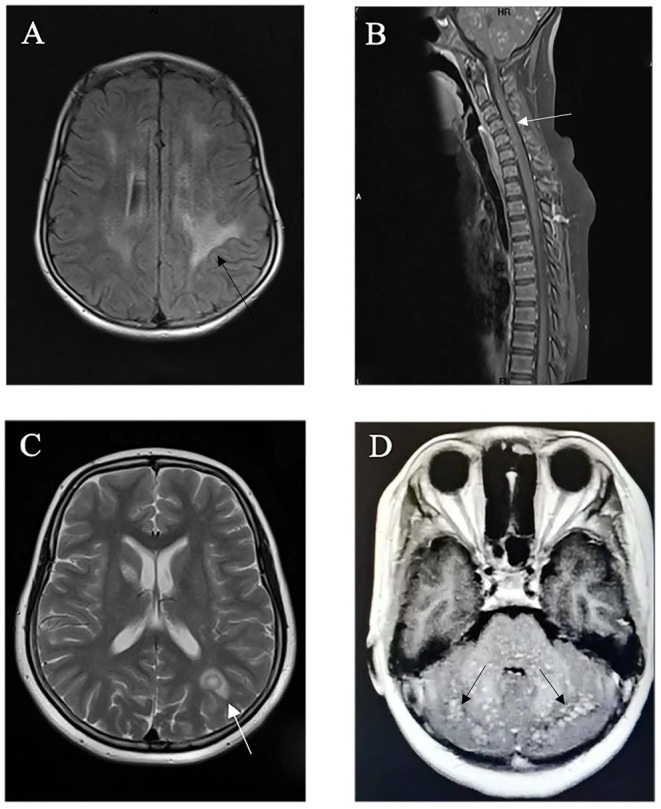

Familial hemophagocytic lymphohistiocytosis (FHL) is a genetic inflammatory response syndrome involving many organs. Central nervous system (CNS)-isolated FHL is a rare, neuroinflammatory condition. Here, we report a case of CNS-isolated FHL3. Brain magnetic resonance imaging (MRI) showed CNS lesions mimicking chronic lymphocytic inflammation with pontine perivascular enhancement responsive to steroids and multiple sclerosis. Whole-exome sequencing (WES) demonstrated likely pathogenic, parentally inherited homozygous variants of UNC13D (c.2588G>A, p.G863D). Neuropathological examination of a brain biopsy specimen revealed lymphocyte infiltration. Reduced levels of CD107a were also observed. CNS-isolated FHL was final diagnosis. The patient's clinical and radiological condition improved after allogeneic hematopoietic stem cell transplantation (HSCT). A study of five isolated CNS FHL3 cases (onset: 7-31 years; three females, one male, and one unknown) identified the hotspot variants c.2588G>A and c.2346_2349del. Possible triggers include the Epstein-Barr virus and herpes simplex virus. Common CNS symptoms included headache, seizures, diplopia, and ataxia (3/5 each). MRI revealed multifocal cerebral/brainstem/spinal cord lesions. Cerebrospinal fluid revealed nonspecific inflammation. Biopsies revealed T-cell predominant lymphocytic infiltration (3/3). Reduced CD107a expression was observed in four patients. Two developed systemic hemophagocytic lymphohistiocytosis (HLH). Steroids (5/5) and intravenous immunoglobulin (4/5) were the primary treatments and HSCT (4/4) achieved good outcomes. One died of HLH. To date, homozygous variants of UNC13D (c.2588G>A, p.G863D) have not been reported in CNS-isolated FHL. Symptoms and brain MRI of CNS-isolated FHL simulate some neuroinflammatory diseases; however, WES and functional analysis may be useful for distinguishing between them. HSCT might be an effective therapeutic strategy.